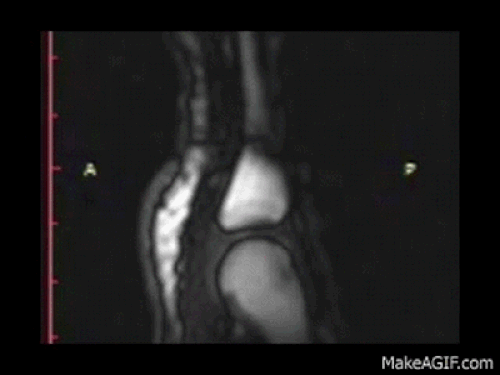

Basitçe anlatırsak; eklem, iki kemiğin birleştiği yer ve eklem kapsülü sıvıyla dolu. Eklemlerimizi her kütlettiğimizde kemikler ortasındaki boşluk genişliyor. Eklem sıvısı kemikler ortasındaki boşluğu doldurmada yetersiz kalıyor, içerideki basınç düşüyor ve gazla dolu bir kabarcık oluşuyor. Duyduğumuz ses ise bu kabarcık kırıldığında çıkan küt sesi.

İşte her şeyin ardındaki o kabarcık!